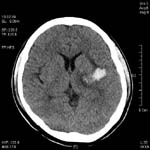

<µÎ°³°ñÀý>

<¼±»ó°ñÀý>

<ÇÔ¸ô°ñÀý>

µÎ°³°ñÀýÀÇ

³úCT ¼Ò°ß

<±Þ¼º°æ¸·¿ÜÃâÇ÷>

<¸¸¼º°æ¸·ÇÏÃâÇ÷>

ÁÂ)

ÁÂÃø ÃøµÎºÎ¿¡ ·»Áî¸ð¾çÀÇ °æ¸·¿Ü ÃâÇ÷ÀÇ

CT¼Ò°ß

¿ì) °æµµÀÇ ¿Ü»ó¿¡µµ

¹ß»ýÇÏ°Ô µÇ´Â ¸¸¼º°æ¸·ÇÏÃâÇ÷ÀÇ ³úMRI¼Ò°ß